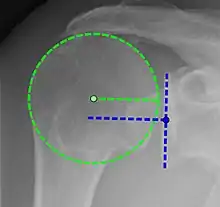

X-ray projectional radiography cannot directly reveal tears of the rotator cuff, a 'soft tissue', and consequently, normal X-rays cannot exclude a damaged cuff. However, indirect evidence of pathology may be seen in instances where one or more of the tendons has undergone degenerative calcification (calcific tendinitis). The humeral head may migrate upward (high-riding humeral head) secondary to tears of the infraspinatus, or combined tears of the supraspinatus and infraspinatus.[52] The migration can be measured by the distance between:

- A line crossing the center of a line between the superior and inferior rims of the glenoid articular surface (blue in image).

- The center of a "best-fit" circle positioned over the humeral articular surface (green in image)

Normally, the former is positioned inferiorly to the latter, and a reversal therefore indicates a rotator cuff tear.[52] Prolonged contact between a high-riding humeral head and the acromion above it may lead to X-ray findings of wear on the humeral head and acromion; secondary degenerative arthritis of the glenohumeral joint (the ball and socket joint of the shoulder), called cuff arthropathy, may follow.[51] Incidental X-ray findings of bone spurs at the adjacent acromioclavicular joint may show a bone spur growing from the outer edge of the clavicle downward toward the rotator cuff. Spurs may also be seen on the underside of the acromion, once thought to cause direct fraying of the rotator cuff from contact friction, a concept currently regarded as controversial.